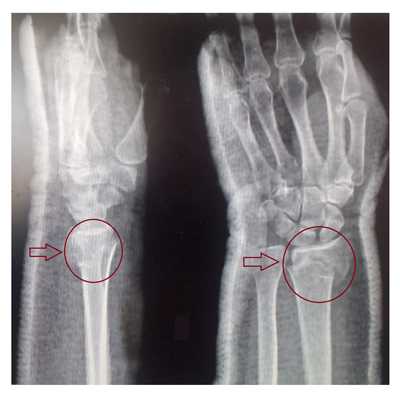

Рентгенография лучезапястного сустава. Перелом дистального метаэпифиза лучевой кости со смещением отломков.

Рентгеновский снимок перелома лучевой кости в типичном месте